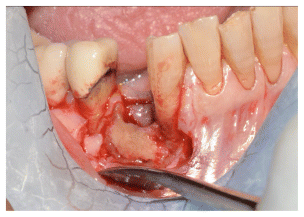

- Epithelial Healing:

Complete epithelialization was observed in 14 out of 15 patients within a median of 3 PRF applications (range: 2–8). In most cases, the first clinical signs of granulation tissue and epithelial closure appeared as early as the second visit. (Figure 2-3-4) - Pain Reduction: